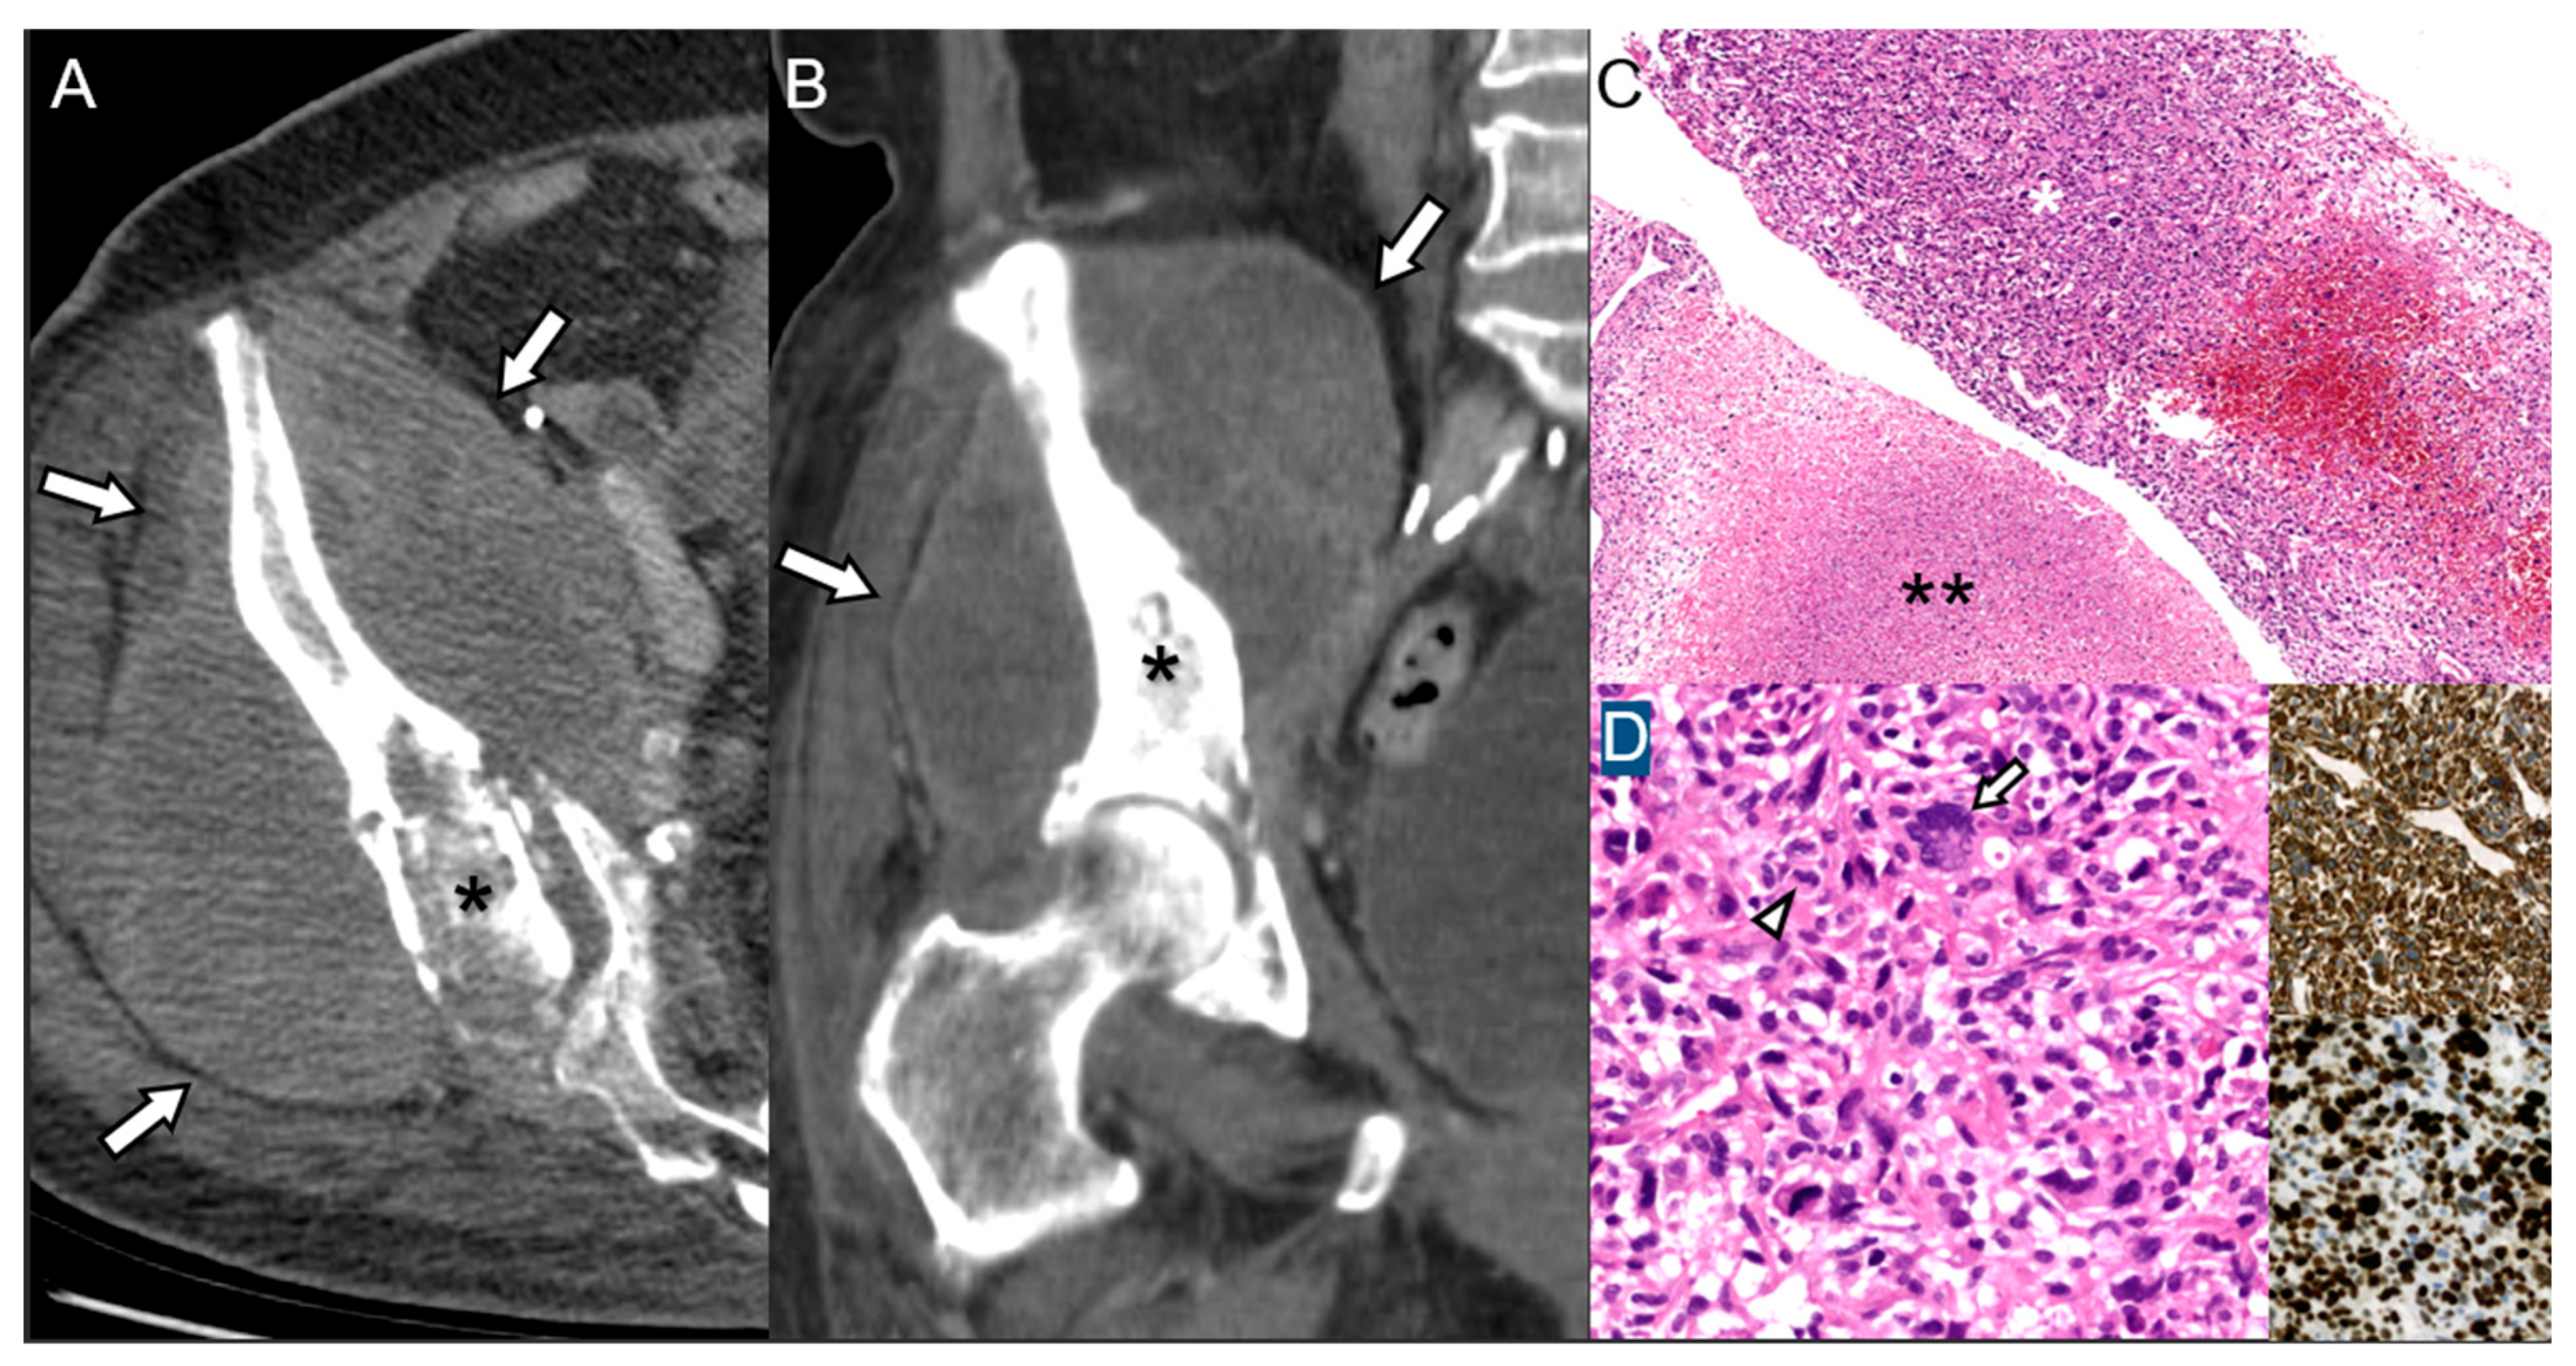

2.3. Giant Cell Tumor of Bone